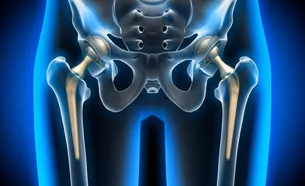

Kalça protezi, bozulmuş olan eklem yüzeylerinin aynı görevi yapacak metal, plastik ve seramikten üretilmiş malzeme ile değiştirilme işlemidir. İlk kez 1960’larda uygulanmaya başlanan protezler, teknolojinin ilerlemesiyle geliştirilerek bugünlere kadar gelmiştir. Ameliyat sırasında hasarlı kemik ve kıkırdak çıkarılır ve yerine protez bileşenleri yerleştirilir.

Hasar görmüş femur başı çıkarılır ve yerine femurun içi boş merkezine yerleştirilen metal bir gövde yerleştirilir.

Sapın üst kısmına metal veya seramik bir küre yerleştirilir. Bu küre, çıkarılan hasarlı femur başının yerini alır.

Yuvanın (asetabulum) hasarlı kıkırdak yüzeyi çıkarılarak yerine metal bir yuva yerleştirilir. Soketi yerinde tutmak için bazen vidalar veya çimento kullanılır.

Pürüzsüz bir kayma yüzeyi sağlamak için yeni top ile yuva arasına plastik, seramik veya metal bir ara parça yerleştirilir.